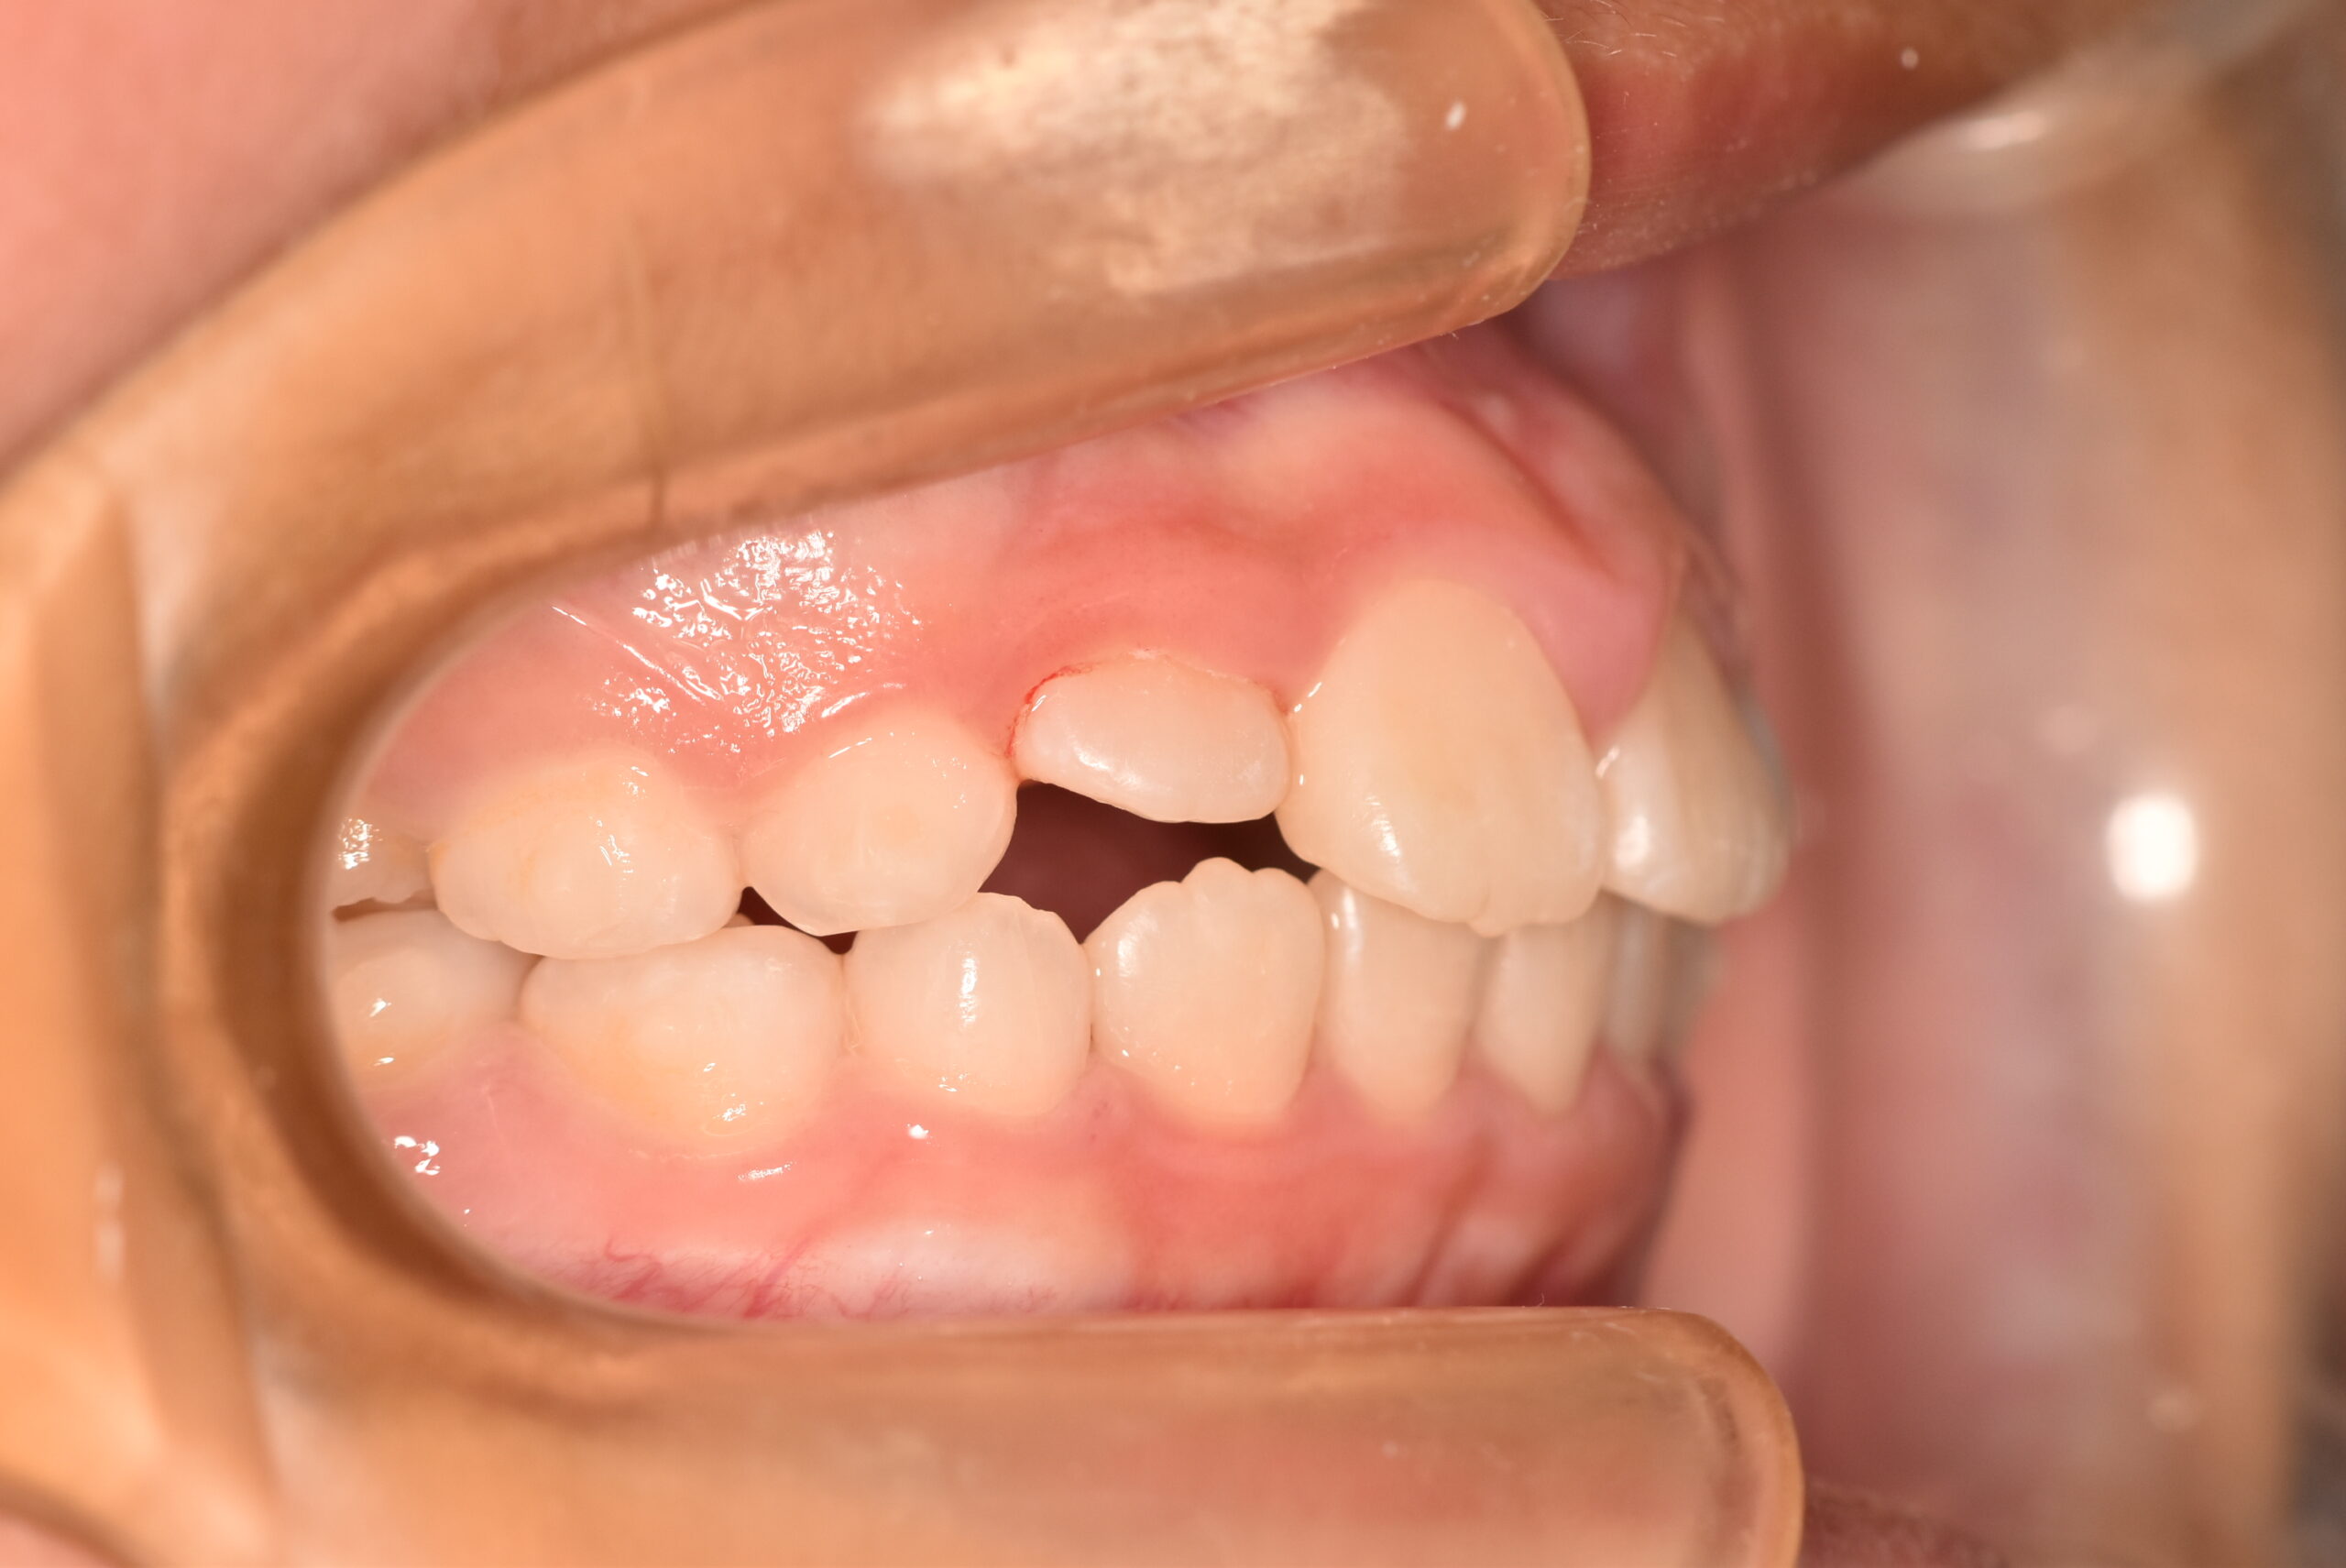

初診時

症例 症例 症例 症例

年齢

9歳 性 別 女性

治療内容の詳細 初診時9歳の女児で、歯のがたつきを気にされ来院されました。

検査の結果、前歯部叢生を伴うアングルⅠ級不正咬合と診断しました。

治療としてはマウスピース矯正(インビザラインファースト)で配列を行い、上下顎の側方拡大と萌出スペースを確保しました。